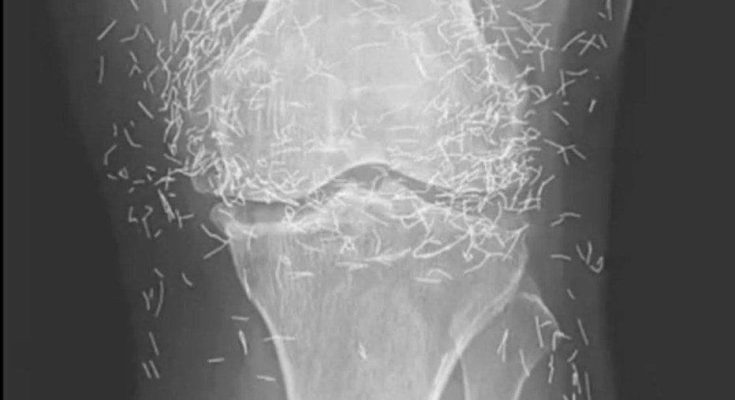

Years later, when doctors took X-rays to evaluate her knee condition, they weren’t prepared for what appeared on the images. Her knees were filled with dozens of bright, metallic flecks — tiny needles embedded deep within the joint area.

The findings were later documented in a case published by the New England Journal of Medicine.